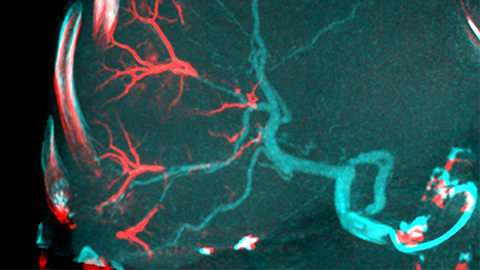

EmboGuide supports you in maximizing the efficacy of your TACE procedures as it potentially enhances your sensitivity, reduces false positives and maximizes inter-reader agreement [4]. It provides efficient, workflow-based live 3D guidance with automatic feeder detection [5].

ClarityIQ produces tuned, high definition low dose images with superb vascular detail to monitor the embolization [6].

A post embolization 3D acquisition allows you to visualize the targeted deposition of embolic material, such as Liopidol or radiopaque beads, in the tumor [7].